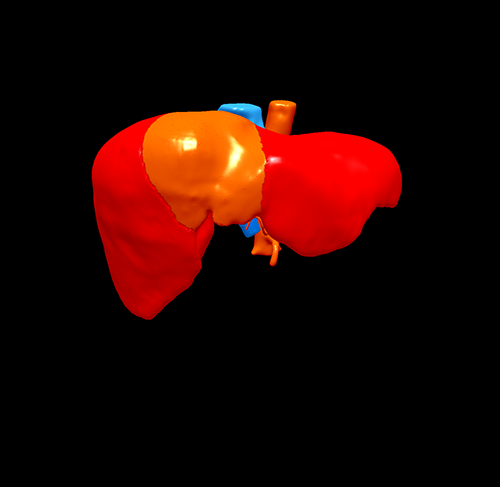

S8肝癌---改良肝中叶切除(3D打印)